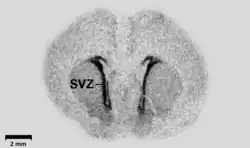

- ^ Haydar TF, Wang F, Schwartz ML, Rakic P (August 2000). "Differential modulation of proliferation in the neocortical ventricular and subventricular zones". J. Neurosci. 20 (15): 5764–74. doi:10.1523/JNEUROSCI.20-15-05764.2000. PMC 3823557. PMID 10908617.

- ^ Behar TN, Schaffner AE, Scott CA, O'Connell C, Barker JL (August 1998). "Differential response of cortical plate and ventricular zone cells to GABA as a migration stimulus". J. Neurosci. 18 (16): 6378–87. doi:10.1523/JNEUROSCI.18-16-06378.1998. PMC 6793175. PMID 9698329.